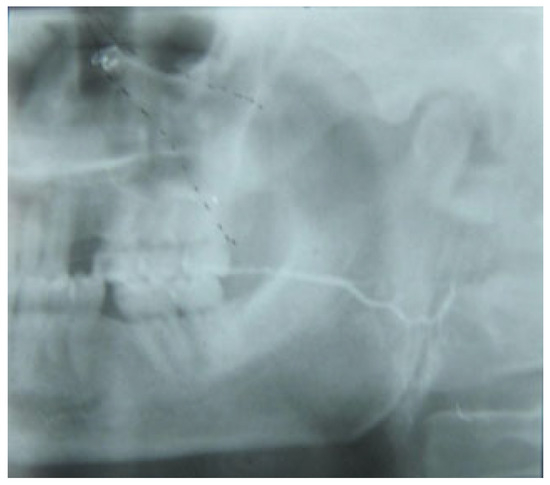

Figure 8. Sialography of the same patient 1 month later. The excretory system of the left parotid gland functions normally. No stenosis of the parotid duct is noticed.